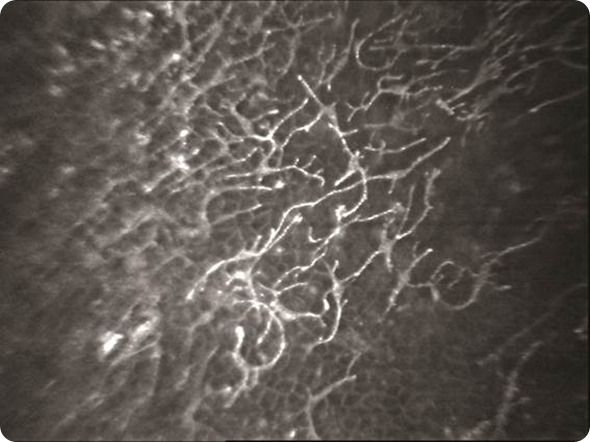

Dendritic cells in the cornea imaged by confocal microscopy.

© LVPEI